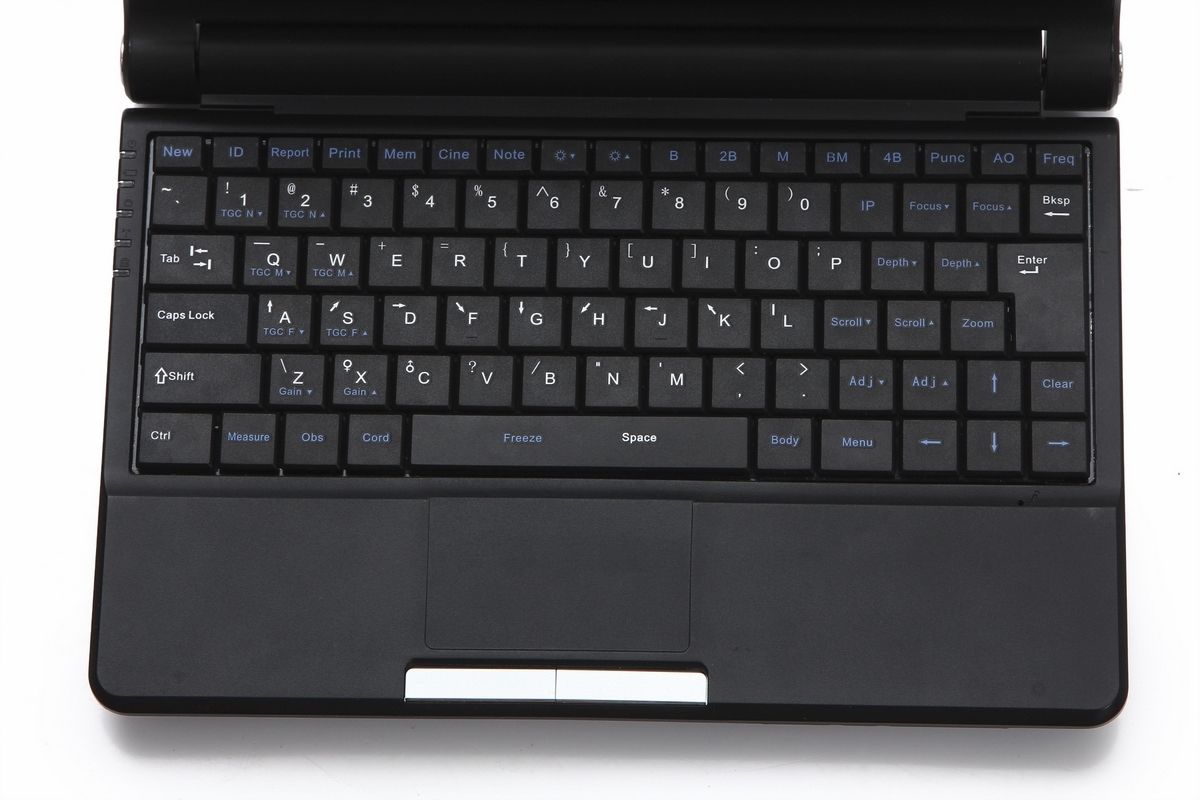

Portability and Convenience

One of the standout features of this ultrasound machine is its portability. The compact design, combined with a carrying case, makes it easy to transport between clinics or even to home visits. This ensures that medical professionals can deliver timely care, regardless of location. Therefore, it’s perfect for practitioners who need versatility in their equipment.

User-Friendly Interface

The Laptop Ultrasound Scanner is equipped with an intuitive interface that simplifies operation. Even those who may not be tech-savvy will find it easy to navigate through various functionalities. Additionally, the visual output on the laptop screen is clear and informative. So, both experienced and novice users can quickly learn how to use the device effectively.